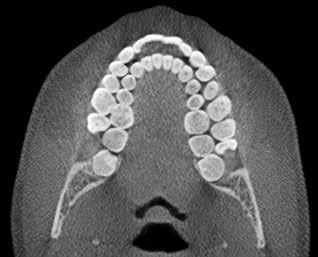

Klik ind på Tandlægebladet.dk og opret en reklamation, så sørger vi for, at bladet lander i din postkasse.

Klik ind på Tandlægebladet.dk og vælg om os

BAGGRUND – Transverselle okklusionsafvigelser kombineret med en vækstbetinget kæbedeformitet korrigeres sædvanligvis ved en sektioneret Le Fort 1-osteotomi eller kirurgisk assisteret ganeekspansion. Ved ekstreme transverselle skeletale diskrepanser mellem maksillen og mandiblen kan der være indikation for transversel udvidelse af mandiblen ved hjælp af mandibulær midtlinjeosteotomi eller mandibulær midtlinjedistraktionsosteogenese.

PATIENTTILFÆLDE – En 15-årig dreng med infantil autisme blev henvist fra Hjørring Kommunes Tandpleje til Kæbekirurgisk Afdeling, Aalborg Universitetshospital, for ortodontisk-kirurgisk behandling af et stort horisontalt maksillært overbid uden kontakt på nogen af tænderne. Den vækstbetingede kæbedeformitet blev korrigeret ved hjælp af ortodonti og mandibulær midtlinjedistraktionsosteogenese efterfulgt af en sektioneret Le Fort I-osteotomi og bilateral sagittal splitosteotomi.

KONKLUSION – Mandibulær midtlinjedistraktionsosteogenese er en forudsigelig behandlingsmodalitet til transversel udvidelse af mandiblen. Imidlertid er behandlingen forbundet med en betydelig risiko for recidiv samt biologiske og tekniske komplikationer, hvorfor mandibulær midtlinjedistraktionsosteogenese udelukkende anbefales til korrektion af ekstreme vækstbetingede transverselle okklusionsafvigelser.

EMNEORD Jaw abnormalities | malocclusion | orthodontics | orthognathic surgery

PERNILLE SAGBAKKEN, tandlæge, Odontologisk Institut, Det Sundhedsvidenskabelige Fakultet, Københavns Universitet

ANNETTE DALGAARD KJELLERUP, specialtandlæge i ortodonti, Kæbekirurgisk Afdeling, Aalborg Universitetshospital